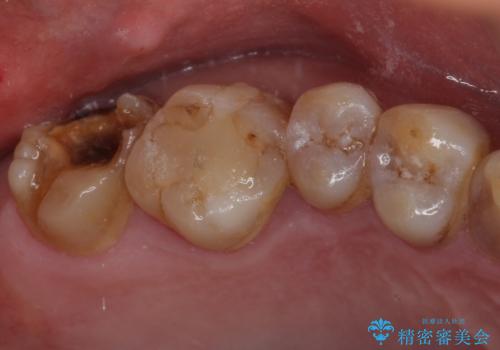

- 銀歯が外れてしまったとのことで来院された患者様です。

上顎奥の粘膜に近い部分で、外れた銀歯の下には大きく虫歯が広がっていました。

虫歯をしっかりと取り除き、ゴールドインレーにて修復することとしました。